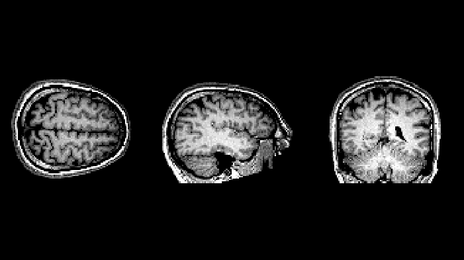

MRI PROTOCOL

This is MRI scanning video and MRI scanning protocol that will help you understand more how the MRI works.